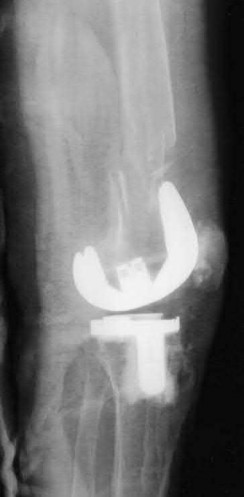

Question 16:

A 65-year-old man presents with anterior knee pain and a feeling of instability during stair climbing 1 year after a primary total knee arthroplasty. Examination reveals a lateral patellar tilt. CT scan is performed to evaluate component rotation. Which of the following errors in component positioning is most likely responsible for his symptoms?

Correct Answer: Internal rotation of the femoral component

Explanation:

Internal rotation of the femoral component or the tibial component increases the Q angle, leading to lateral patellar maltracking, lateral patellar tilt, and anterior knee pain. External rotation of the components generally improves patellar tracking.